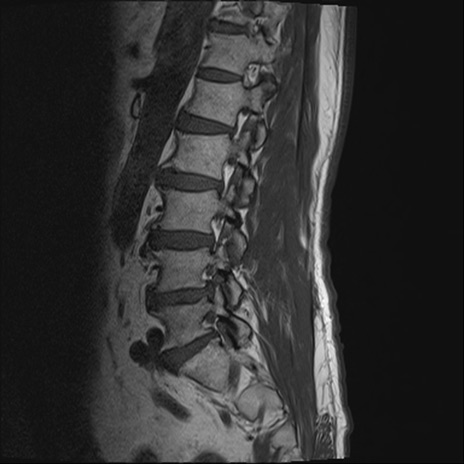

【整形】TIPS症例2 腰椎MRI T1WI(矢状断像)

【症例】70歳代男性

【主訴】左下肢痛

【現病歴】2週間前くらいから腰痛、左下肢痛あり。左臀部から大腿、下腿外側のしびれが常時ある。歩行とともに同部位の痛みあり。

【身体所見】Lasegue70-/60+、Bragard-/±、PTR ±/±、ATR -/-、IP 5/5、TA 5/4、TS 5/5、EHL 右第1足趾なし/3、FHL 5/5、hypersthesia(-)、足背動脈触知良好

異常所見と診断は?